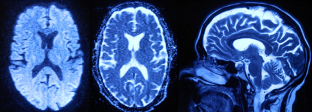

Chikungunya infection presenting as mild encephalitis with a reversible lesion in the splenium: a case report

Chikungunya fever is an Aedes mosquito-transmitted infection caused by chikungunya virus, an RNA virus in the family Togaviridae. The disease is characteristically manifested as fever, arthralgia, and/or rash. Various neurological manifestations like meningoencephalitis, myelitis, and myeloneuropathy have been mentioned in various reports. We present a rare case of chikungunya fever presenting with mild encephalitis with a reversible lesion of the splenium (MERS), which showed complete clinical and radiological recovery.

Fig. 2